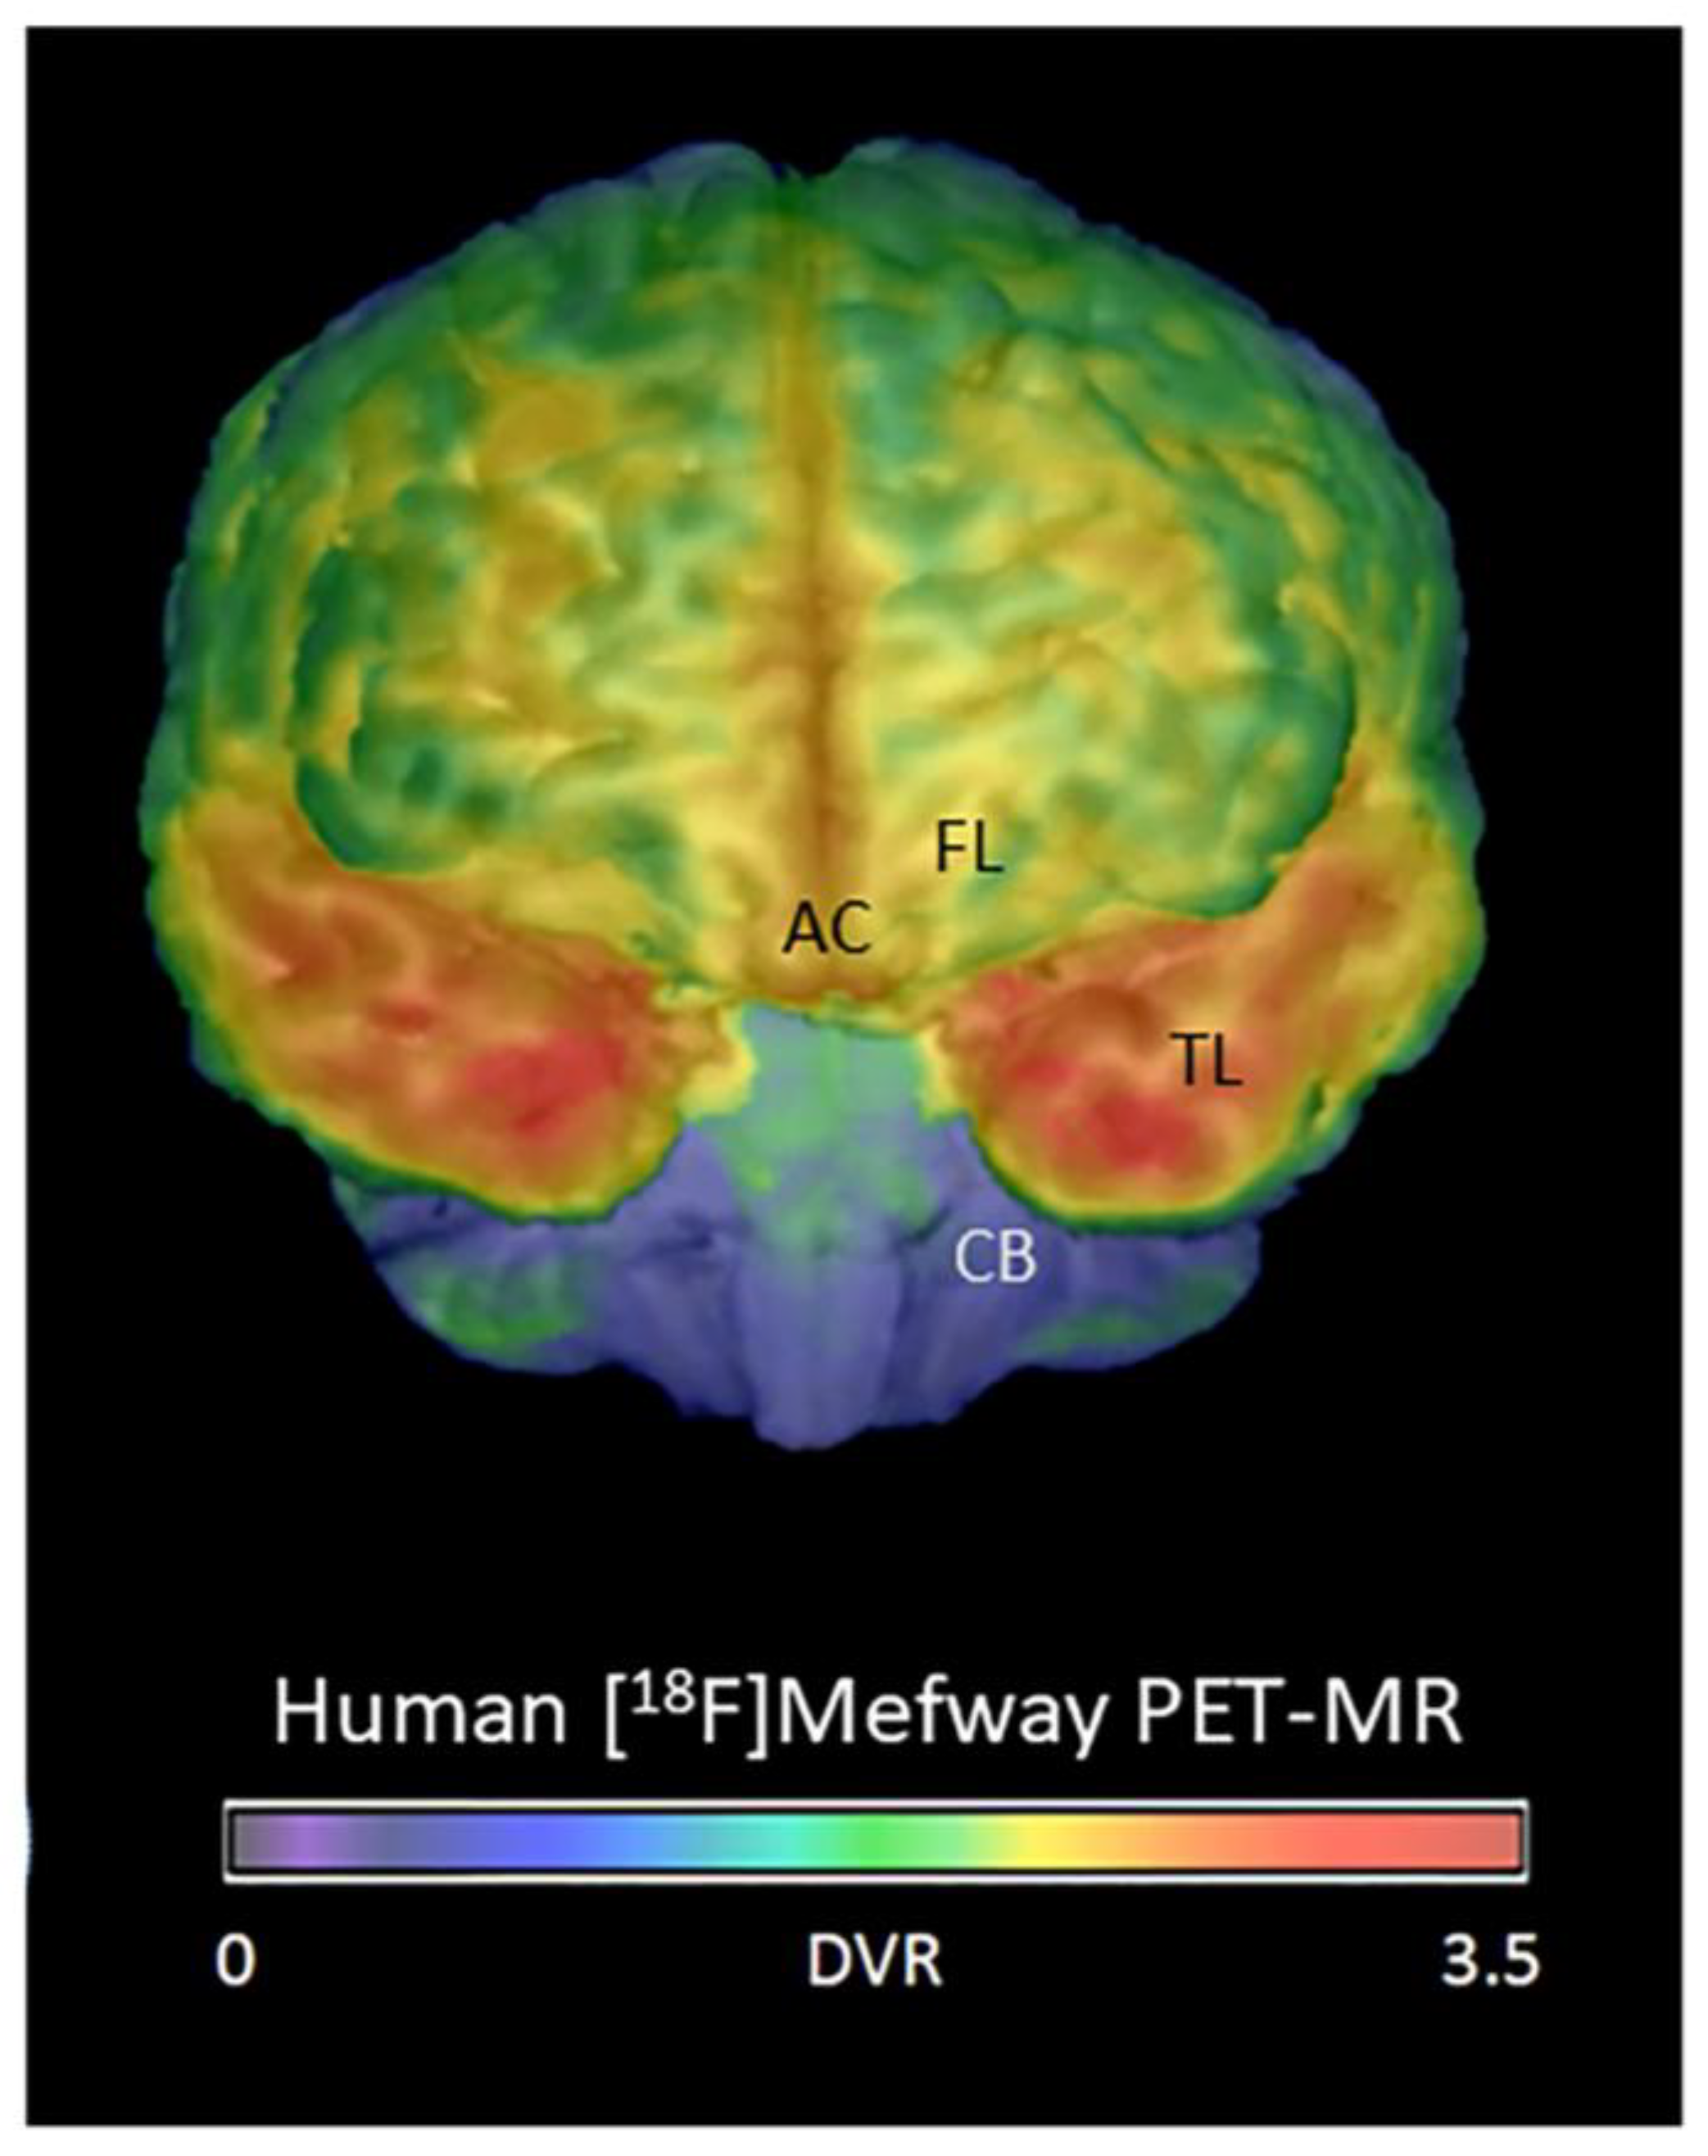

- Mukherjee, J.; Bajwa, A.K.; Wooten, D.W.; Hillmer, A.T.; Pan, M.-L.; Pandey, S.K.; Saigal, N.; Christian, B.T. Comparative assessment of 18F-Mefway as a serotonin 5-HT1A receptor PET imaging agent across species-rodents, nonhuman primates and humans. J. Comp. Neurol. 2016, 524, 1457–1471. [Google Scholar] [CrossRef]